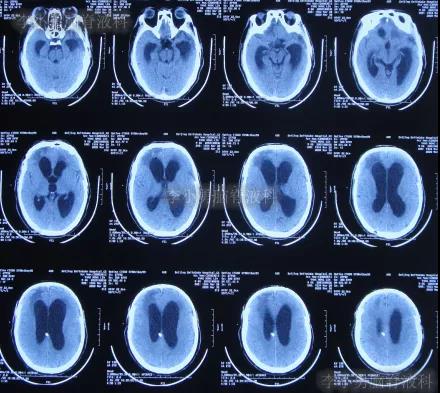

2020年3月18日(颅脑外伤开颅术后149天即颅骨修补术后95天即第2次脑室腹腔分流术后62天,先后经4家医院治疗后仍意识模糊,大小便失禁,脑积水,间断发热近2月)转住入李小勇脑脊液科。入院时:意识模糊,大小便失禁,体重较前明显减轻,体温高38度左右;头部可见引流管走向;右侧肢体活动差些;鼻饲流食(图-30);入院时头颅CT示颅骨修补术后、脑室引流术后仍脑积水,有水肿(图-31)。

图-31:2020年3月18日头颅CT